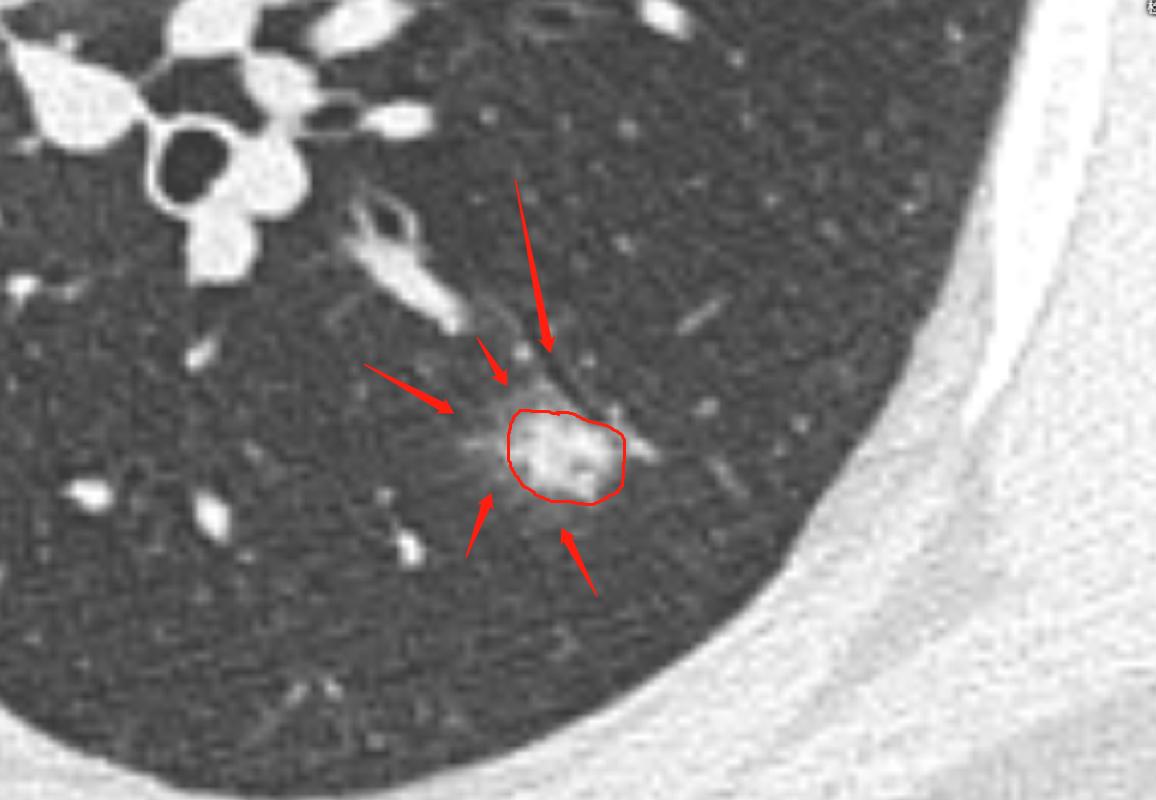

影像学是建立在高清影像的基础上的诊断,首先我们的图片要清楚,以下是患者家属提供的DICOM数据,分析时得到的图片。很多时候诊断不清楚,就是因为影像资料不清楚。

通过以上图片,病灶确实为实性结节,大小约1.0cm×0.9cm×1.0cm,呈浅分叶,周边可见毛刺,可见小血管穿入,但是影像学还是有一些不符合恶性肿瘤的特点:

1.病灶周边有一些渗出性改变。

2.相对1cm大小的肺结节来说,周边的毛刺有点长。

3.病灶及周边有扩张的支气管影。

4.病灶周边血管明显有贴边征象。

5.病灶两个月前 大小约0.6cm×0.8cm,这一点还是很重要的,如果我们在看诊过程中只带胶片,很难比较的。

6.双肺还有多发类似实性小结节,病灶均较为模糊,虽然是实性结节,但相对更趋于新发的可能,没有纤维化。